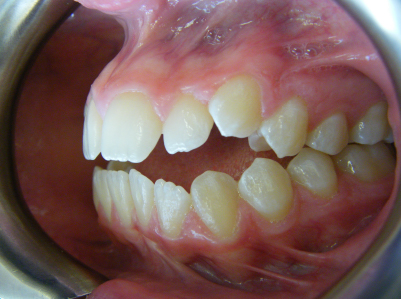

Patient 2: Significant increased overjet and upper and lower crowding.